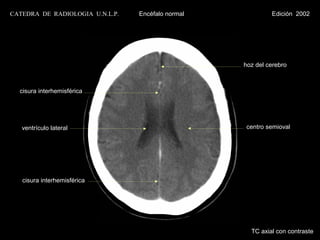

CATEDRA DE RADIOLOGIA U.N.L.P.   Encéfalo normal            Edición 2002

cisura interhemisférica

cuerpo calloso

ventrículo lateral                              septum pelucidum

centro semioval

plexo coroideo                                  glándula pineal

calcificado                                     calcificada

asta occipital

seno longitudinal inferior

seno longitudinal superior

TC axial con contraste